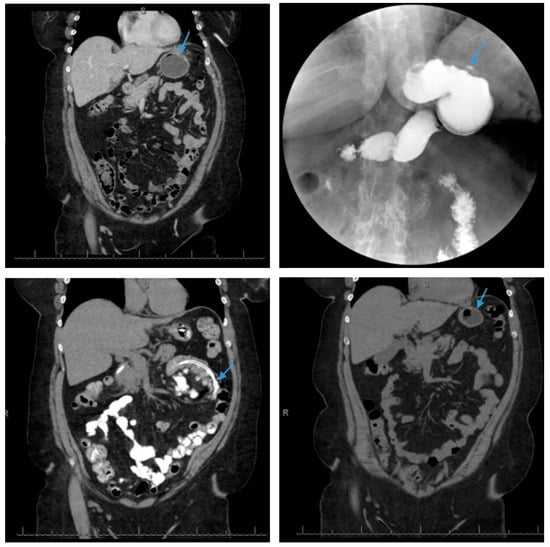

Scheme 1.

Lateral and transverse (top left and top right) views of a computed tomography scan of the abdomen and pelvis reveals air-fluid collections adjacent to the fundus of the stomach (3.3 × 3.0 cm) (arrow, top left), anterior to the stomach (2.2 × 4.6 cm) and in the epigastric region of the abdominal wall (6.2 × 3.0 cm) (arrows, top right), which likely represents abscesses in the setting of staple line dehiscence. Axial views of the computed tomography scan of the abdomen and pelvis (bottom left and bottom right) redemonstrate the somewhat ill-defined collection of gas and (arrows, bottom left and bottom right) fluid likely due to focal dehiscence and an abscess cavity which is the source of a gastrocutaneous fistula.

Coronal view of a computed tomography scan of the abdomen and pelvis reveals a small, contained leak (arrow, top left) along the greater curvature of the gastric body in a patient following sleeve gastrectomy. Upper gastrointestinal series demonstrates a small amount of extravasated contrast along the greater curvature of the gastric body with no free spill of extravasated contrast which is consistent with a small, contained perforation (arrow, top right) in a patient post-sleeve gastrectomy. The patient was treated with nothing per os and nasojejunal tube feeds (arrow, bottom left) for two weeks, with the resolution of sleeve leak and the removal of the nasojejunal tube (arrow, bottom right) as demonstrated on a follow-up coronal view of a computed tomography scan of the abdomen and pelvis.